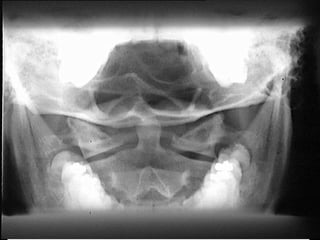

INCIDÊNCIA ANTERO-POSTERIOR  (AP) VIAS ÁEREAS SUPERIORES

Posição do Paciente:  Ortost á tica, se poss í vel, sentado ou em p é , com a parte posterior da cabe ç a e os dos ombros contra o chassi (pode ser realizada em dec ú bito, se necess á rio);   Alinhando o plano mediosagital com o RC e com a linha m é dia da grade ou da mesa. Elevar o queixo de modo que a linha  acantiomeatal esteja perpendicular ao chassi (a linha do acantio ou  á rea diretamente abaixo do nariz e do meato ou MAE); o paciente deve olhar diretamente para a frente. Ajustar a altura do chassi, de modo a colocar a sua parte superior 3 a 4 cm (1 a 1 1/2 polegada) abaixo do MAE; Raio Central:   Perpendicular ao centro do chassi ao n í vel de T1, cerca de 2,5 cm acima da incisura   jugular; DFoFi:  m í nimo, 102 cm  (40  polegadas); Colima ç ão:  Colimar a  á rea de interesse; Respira ç ão:  A exposi ç ão  é  feita durante uma inspira ç ão lenta e profunda para garantir o enchimento da traqu é ia e das vias respirat ó rias altas com ar.

Observa ç ão:  S obre a exposi ç ão: A exposi ç ão para essa incidência. AP deve ser aproximadamente igual  à  de uma incidência AP para coluna vertebral cervical e/ou tor á cica. Estruturas Mostradas:   A laringe e a traqu é ia, de C3 a T 4, devem estar repletas de ar e visualizadas atrav é s da coluna. A  á rea das v é rtebras cênicas proximais (a margem inferior da sombra da mand í bula e da base do crânio sobrepostas) at é  a região m é dia do t ó rax deve estar inclu í da. Posi ç ão sem rota ç ão, evidenciado pela aparência sim é trica das articula ç ões estenoclaviculares. A mand í bula deve  sobrepor  a base do crânio, com a coluna alinhada com o centro do filme ; Crit é rios de Exposi ç ão :  A exposi ç ão ideal deve ser apenas escura o suficiente para visualizar a traqu é ia repleta de ar atrav é s das v é rtebras cervicais e tor á cicas.